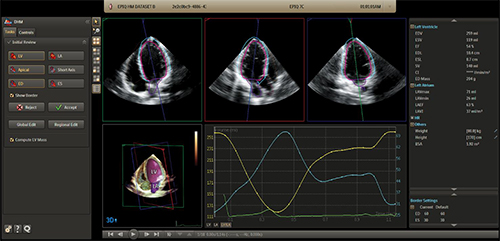

2. アナトミカル・インテリジェンス(AIUS)によるフルサイクルの心臓定量化(Dynamic HeartModelA.I.)

現代では,かつてない量のデータを利用することができるようになった。そのため,再現性のあるデータを取得して価値のある情報に変換し,診断や治療のガイドとするためのプロセスを,より簡単かつ迅速に行えるツールが必要である。AIUSは,解剖学的知識に基づく自動化により,数ステップで再現性の高い結果を取得することを可能にした。新しいアプリケーションである,「Dynamic HeartModelA.I.」は,左室(LV)および左心房(LA)の心周期でのVolumeカーブを表示し,また,LV mass,LVおよびLAのCardiac Indexも解析可能。さらに,1回の動画保存から複数の心拍を解析し,任意の複数の心拍から平均値を算出することができる。